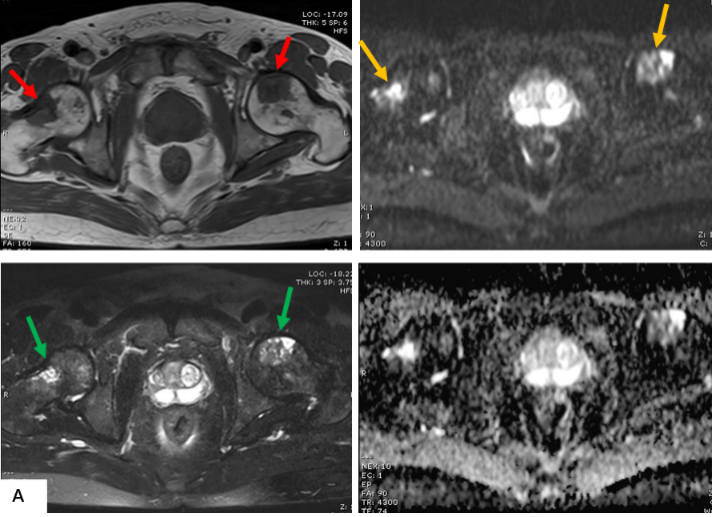

前列腺M(fèi)RI示:前列腺移行帶結(jié)節(jié)狀異常信號(hào),建議穿刺活檢;前列腺增生,PI-RADS2;雙側(cè)股骨頭信號(hào)異常,不排除轉(zhuǎn)移瘤(圖A)。為評(píng)估骨轉(zhuǎn)移情況遂行ECT全身骨顯像檢查,示:雙側(cè)肱骨頭、雙側(cè)股骨頭、右側(cè)前臂上段、右側(cè)股骨中下段代謝異常增強(qiáng)(圖B)。骨顯像不符合前列腺癌骨轉(zhuǎn)移典型表現(xiàn),同時(shí)結(jié)合患者胸部CT(圖C)平掃示右側(cè)腋窩多發(fā)淋巴結(jié)腫大,生化檢查示乳酸脫氫酶620U/L(97-270),懷疑系血液系統(tǒng)腫瘤,建議患者行PET/CT檢查。PET/CT示:右側(cè)腦室內(nèi)高密度灶,多發(fā)FDG代謝增高淋巴結(jié)及多發(fā)骨骼/骨髓FDG代謝增高灶,考慮淋巴瘤(圖D)。

MR示雙側(cè)股骨頭見(jiàn)斑片狀壓脂高信號(hào)(綠箭),T1WI信號(hào)減低(紅箭), DWI呈混雜高信號(hào)(黃箭)。